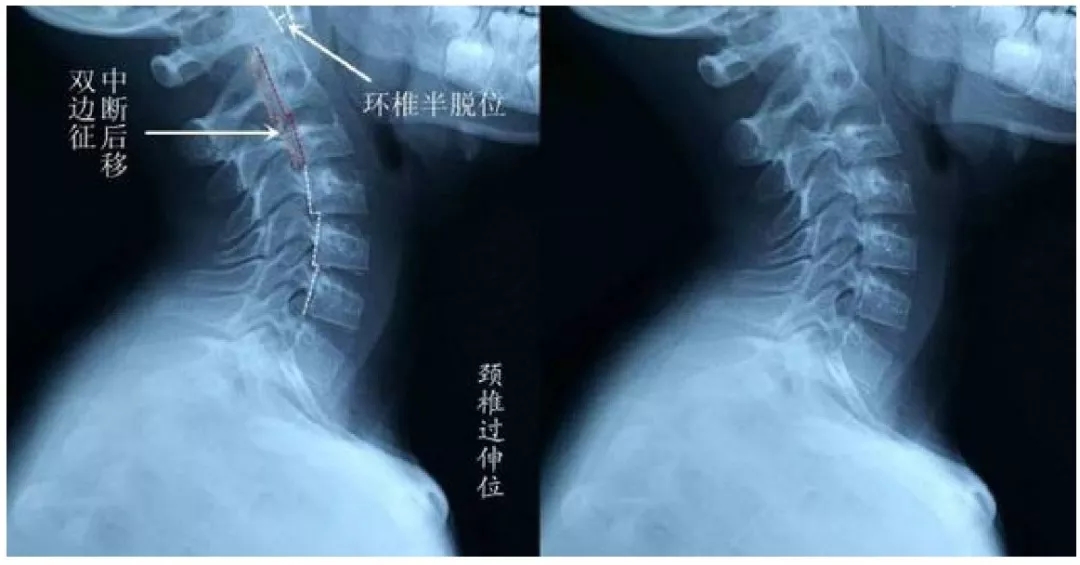

头颈部外伤后导致的头痛和上三个颈椎有关,其机制可能是颈椎损伤后刺激颈神经。在某些情况下,可出现枕大神经痛。

颈椎关节在大脑维持全身姿势中发挥着重要反馈作用。这些关节对错位的损伤非常敏感。颈源性头痛的机制就是颈椎关节功能紊乱导致的。